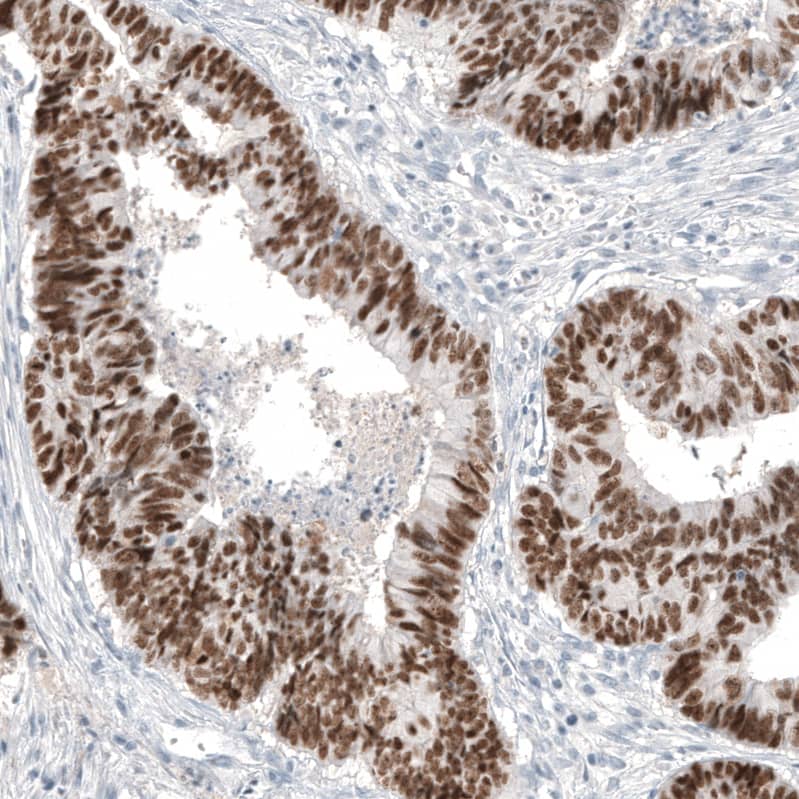

Staining of human colorectal cancer (metastasis to ovary) shows moderate to strong nuclear positivity in tumor cells.

Staining of human colon shows moderate to strong nuclear positivity in glandular cells.

Staining of human colorectal cancer shows strong nuclear positivity in tumor cells.

Staining of human rectum shows strong nuclear positivity in glandular cells.